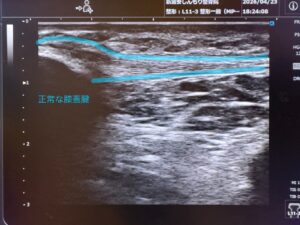

ジャンパー膝とは、正式には膝蓋腱炎(しつがいけんえん)と呼ばれるスポーツ障害です。

近年では、炎症だけでなく腱の変性が主体であることから、膝蓋腱症(Patellar tendinopathy)と表現されることも増えています。

- 腱の肥厚・強度低下

- コラーゲン配列の乱れ(腱の変性)

- 異常血管・神経の新生